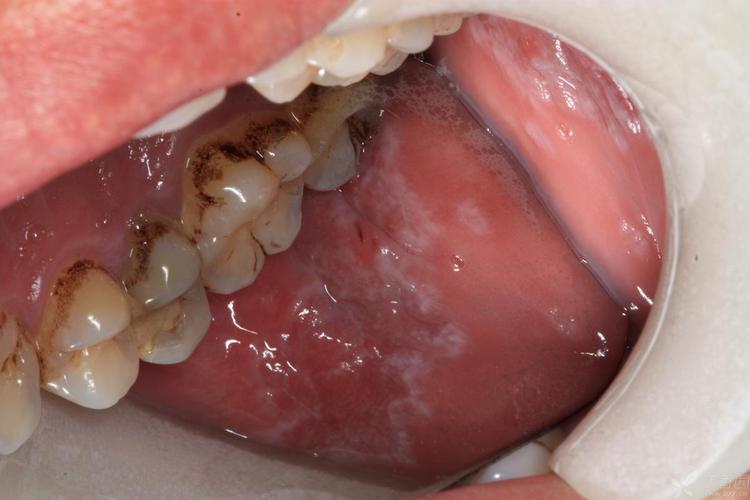

(图片来源网络,侵删)

- 作用机制:长期的精神压力会影响人体的神经-内分泌-免疫网络,导致免疫系统功能失衡,从而诱发或加重扁平苔藓,可以说,“压力”是扁平苔藓最常见的朋友之一。

局部刺激因素

口腔内的物理或化学刺激物也可能诱发或加重病变,这个过程在医学上称为“同形反应”(Koebner phenomenon),即正常的皮肤或黏膜在受到损伤后,在相同部位出现新的病变。

- 机械刺激:

- 尖锐的牙尖、残根、不良修复体(如假牙边缘不光滑):长期、反复的摩擦和刺激是最常见的局部诱因。

- 吸烟:吸烟是OLP发病和病情活动的重要危险因素,烟草中的尼古丁等有害物质会直接刺激黏膜,影响局部微循环和免疫功能。